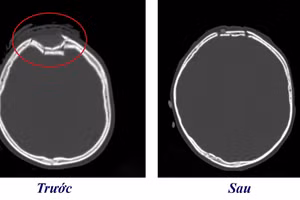

GD&TĐ - Bệnh viện Trung ương Quân đội 108 cảnh báo có nhiều người gặp tai nạn khi lao động để lại nhiều di chứng, trong đó có chấn thương sọ não nặng...